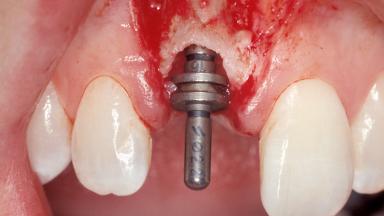

A 30-year-old female patient was referred to the office for the treatment of tooth 11. Her chief concern at the initial visit was to inquire, “Why is my tooth pink?” Upon clinical examination, it was determined that tooth 11 had a previous history of trauma and that the clinical crown had become noticeably pink in color as a result of internal resorption. This diagnosis was confirmed radiographically, indicating a large radiolucency involving the central and distal portions of the clinical crown. It was determined that restoration of this tooth was not possible, and that extraction was indicated. The presence of a mid-line diastema, which the patient wanted to reproduce, directed the treatment plan for tooth replacement utilizing a dental implant.

Type of Implants One-Piece|Reduced-Diameter

Bone Augmentation Horizontal|Simultaneous

Augmentation Materials Autogenous chips|Membrane

Placement Protocol Immediate implant placement

Tooth Site Maxillary incisor or canine

Socket Morphology Single-root socket

Socket Integrity Sufficient, with intact bone walls

Bone Volume Sufficient, with intact walls